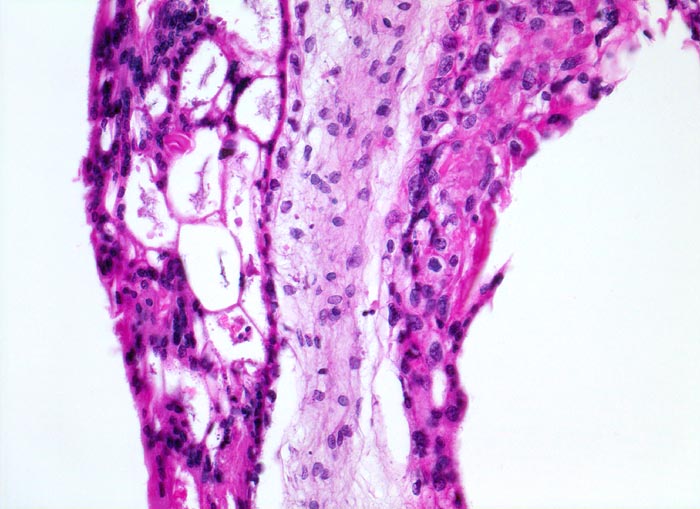

PathoPic ID 5127 - Blasenmole

Blasenmole

angeboren /genetisch/Missbildung

Abortmaterial

Paidopathologie

Ausgeprägte Proliferation von

Syncytio- und

Zytotrophoblastepithel.

beta HCG Level von 150'000 mIU/mL. Uterus zu gross für das Gestationsalter von 10 Wochen. Arterielle Hypertonie.

Histologie

200

32